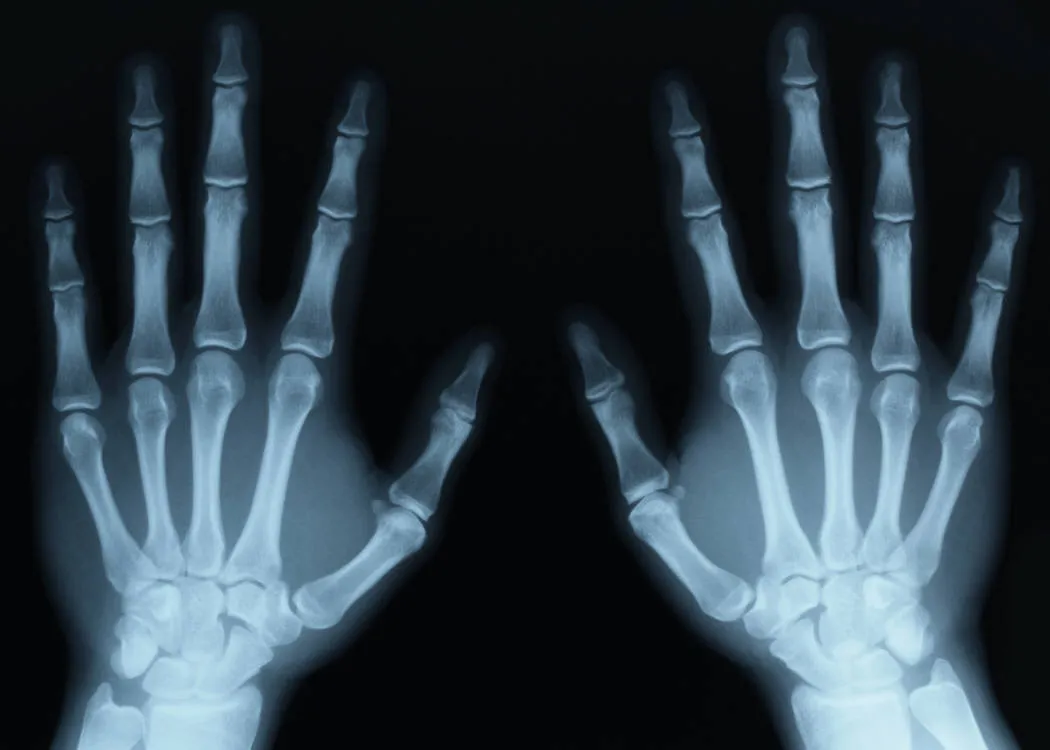

X-ray image of two hands

Dense parts of your body that X-rays find it more difficult to pass through, such as bone, show up as clear white areas on the image. Softer parts that X-rays can pass through more easily, such as your heart & lungs, show up as darker areas.